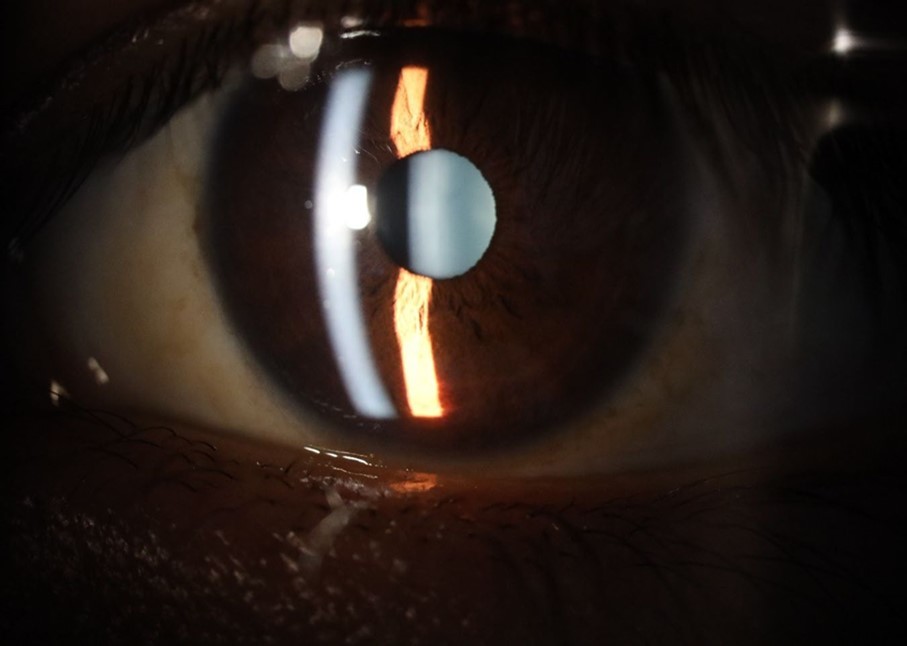

Figure 25.Mirror reflection of the affected eye (right side), with good appearance. This indicates that the transparent media of the eyeball (Cornea, anterior chamber, lens, and vitreous) are in good condition.

Figure 26.The macrograph of the anterior segment of the right eye (affected) shows very good transparency of the cornea, anterior chamber, lens, and vitreous.

Figure 32.The macro photograph of the right eye shows us a cornea, anterior camera, and crystalline lens in very good condition.

Figure 33.The 3 previous photographs show that whitish mass has almost completely disappeared, and to date only a remnant remains on the left side of the photograph. The chorioretinal scar that is now observed corresponds to the area affected by the blunt trauma, which presumably caused rupture of Bruch's membrane. Fortunately, the macular region has recovered almost in its entirety, so the impairment in central vision was minimal.